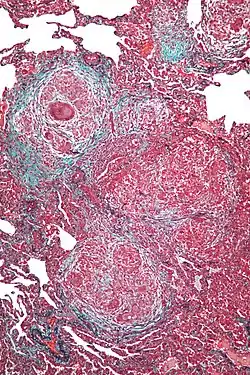

| תמונה היסטולוגית של דלקת ריאות מרגישות יתר כרונית | ||

מאפיין היסטולוגי נפוץ בדלקת ריאות מרגישות יתר הוא גרנולומות לא גבינתיות, סמוך לדרכי האוויר הקטנות, שאינן מתוחמות היטב. עוד נצפים תסנינים, לימפוציטריים ברובם, בפיזור כתמי בנאדיות וברקמת החיבור (אינטרסטיציום). בדלקת כרונית מופיעים שינויים לייפתיים מקומיים, כאשר במחלה מתקדמת הם הופכים להיות נרחבים וחמורים עם מאפייני חלת דבש.

התמונה ההיסטולוגית של גרנולומות בריאה מופיעה גם במחלות אחרות, דוגמת סרקואידוזיס, אך סרקואידוזיס היא מחלה עם ביטוי בשאר מערכות הגוף, והגרנולומות בה מוגדרות היטב, בניגוד לדלקת ריאות מרגישות יתר.